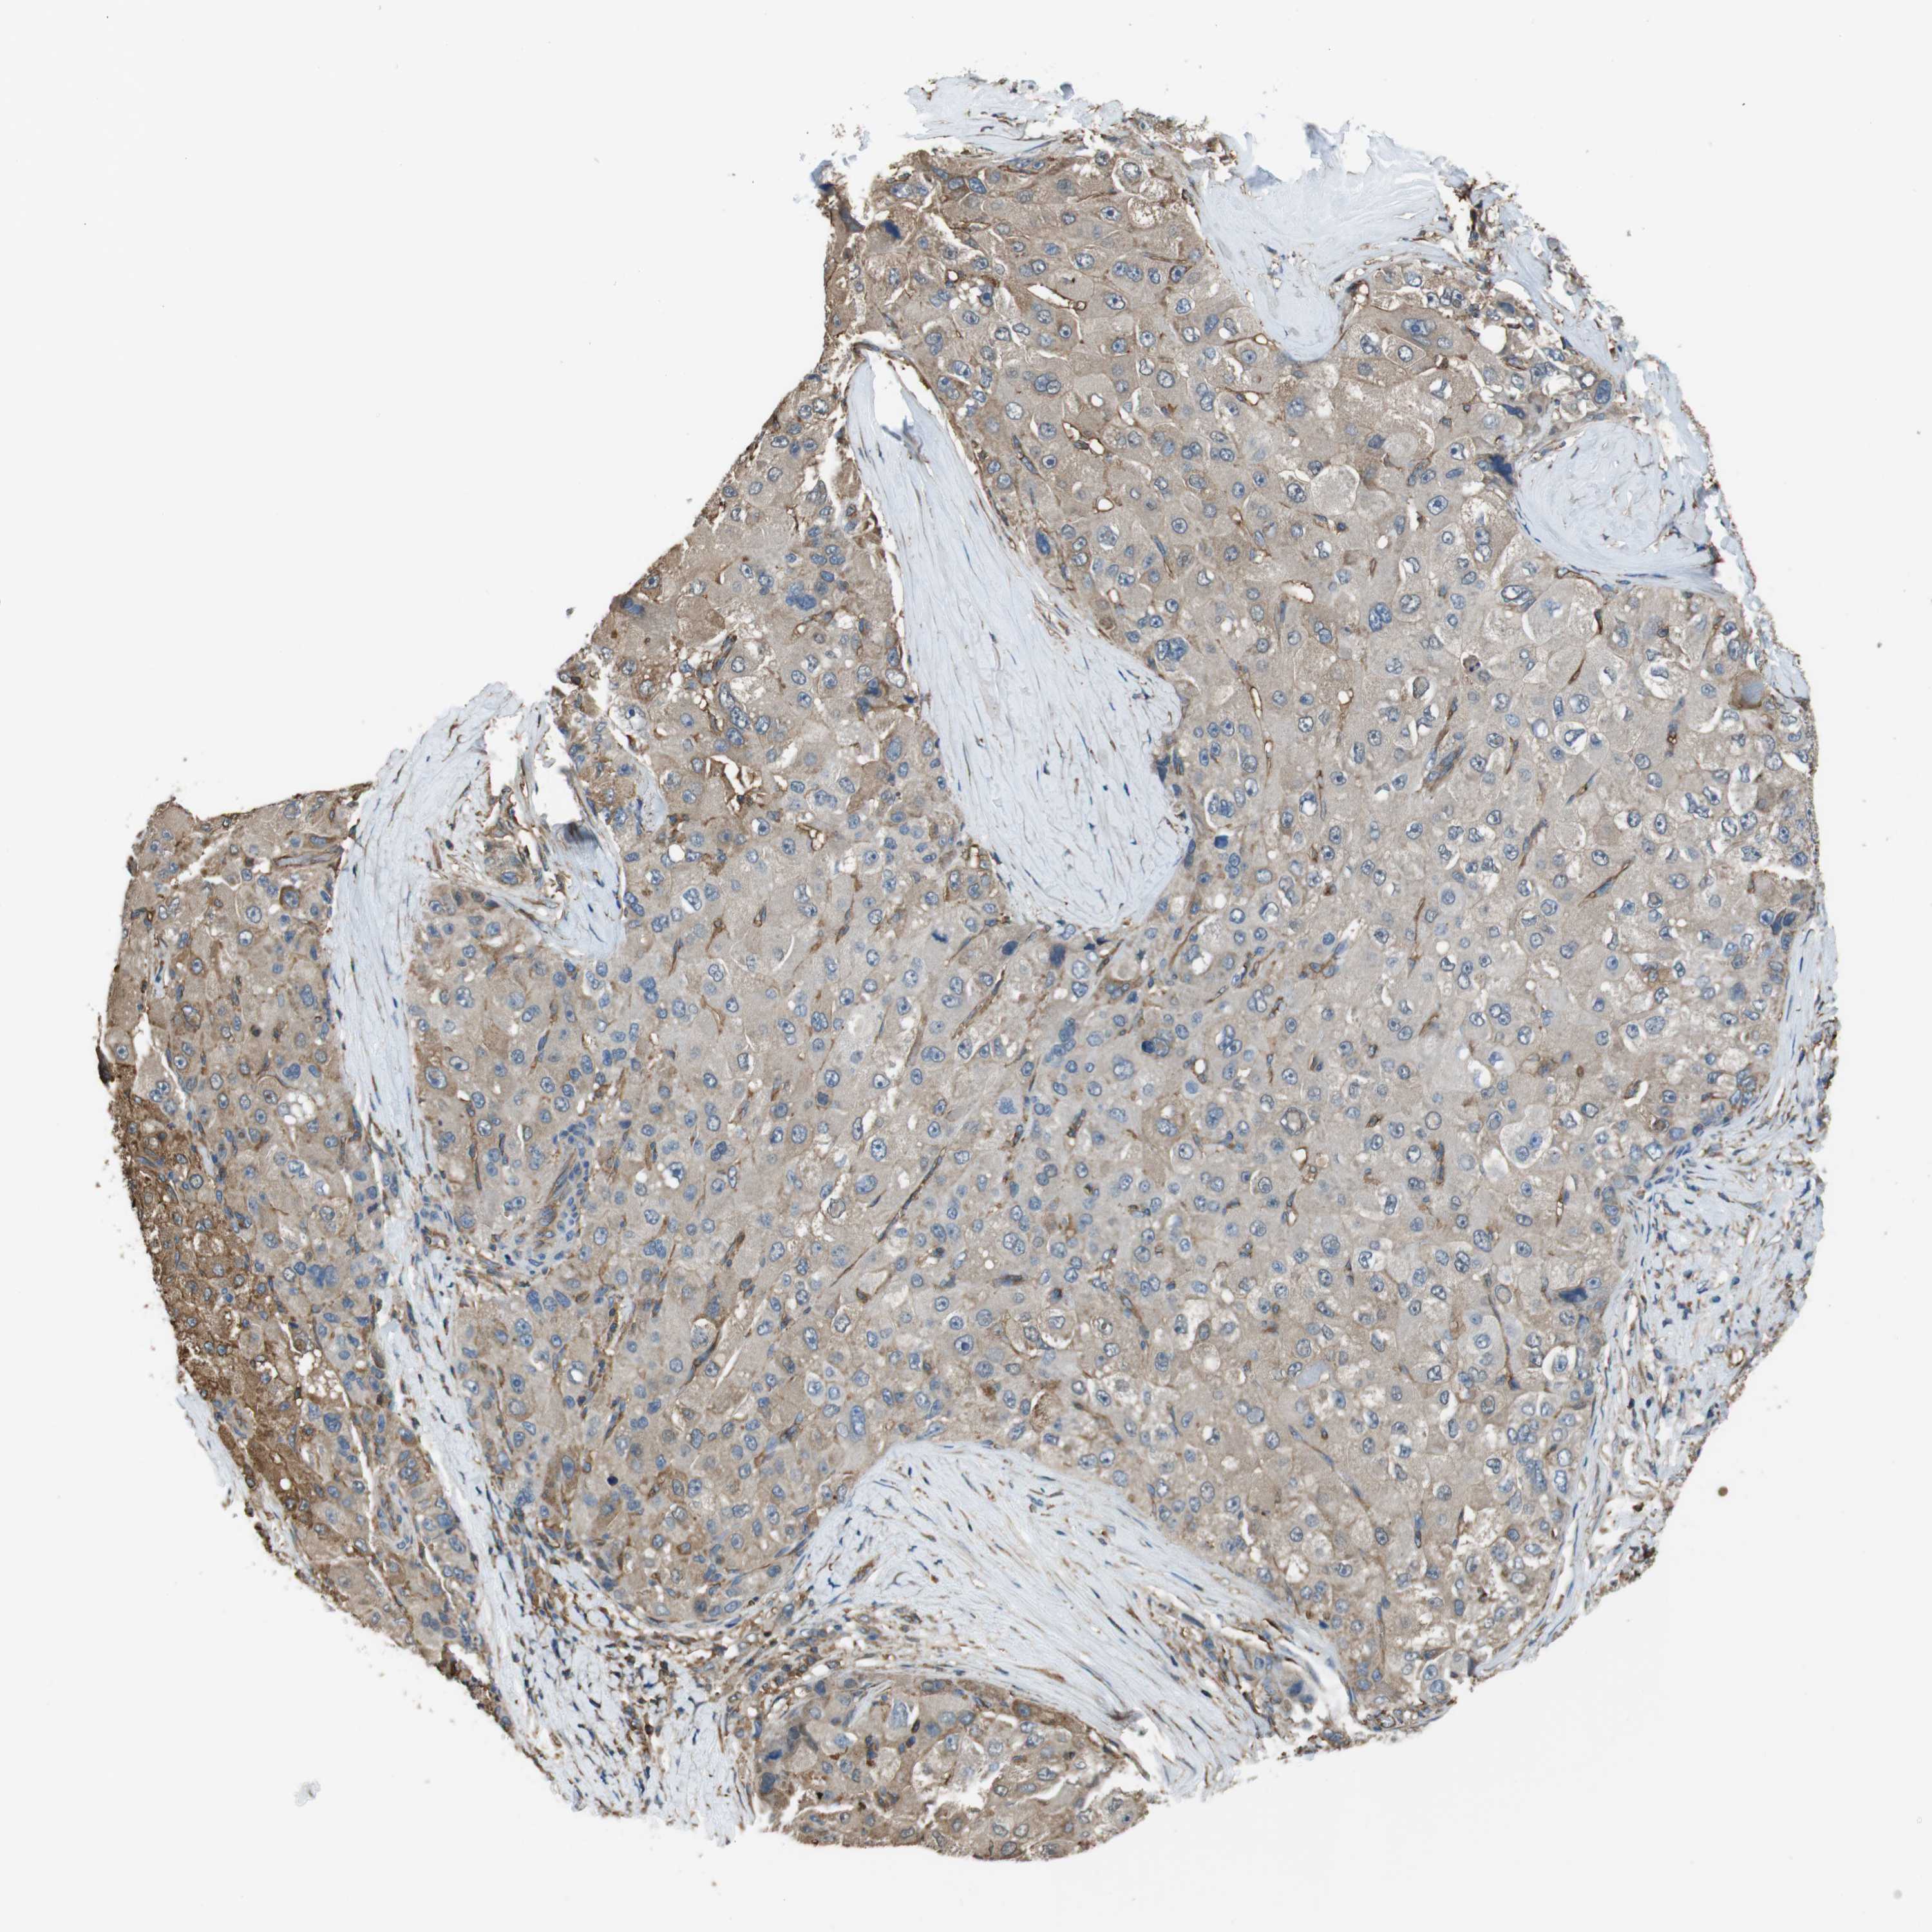

LIVER CANCER - Protein expressioni

A mouse-over function shows sample information and annotation data. Click on an image to view it in a full screen mode. Samples can be filtered based on level of antibody staining by selecting one or several of the following categories: high, medium, low and not detected. The assay and annotation is described here.

Antibody stainingi

Antibody staining in the annotated cell types in the current human tissue is reported as not detected, low, medium, or high, based on conventional immunohistochemistry profiling in selected tissues. This score is based on the combination of the staining intensity and fraction of stained cells.

Each image is clickable and will lead to virtual microscopy that enables deeper exploration of all samples and also displays staining intensity scores, fraction scores and subcellular localization as well as patient and tissue information for each sample.

Antibody HPA014050

Staining

High

Medium

Low

Not detected

Intensity

Strong

Moderate

Weak

Negative

Quantity

>75%

75%-25%

<25%

None

Location

Nuclear

Cytoplasmic/membranous

Cytoplasmic/membranous,nuclear

Cholangiocarcinoma

Carcinoma, Hepatocellular, NOS